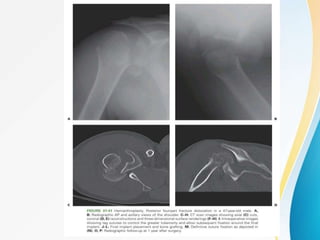

HEMIARTHROPLASTY :

• Also known as Humeral Head Replacement .

• Indications :

1. unreconstructable humeral head

- comminuted head splitting #

- Head depression # involving >40 articular surface

2. biologic viability severely compromised .

• Hertel → # at anatomic neck of humerus had

increased risk of humeral head ischaemia .

• Glenoid erosion → delayed shoulder pain